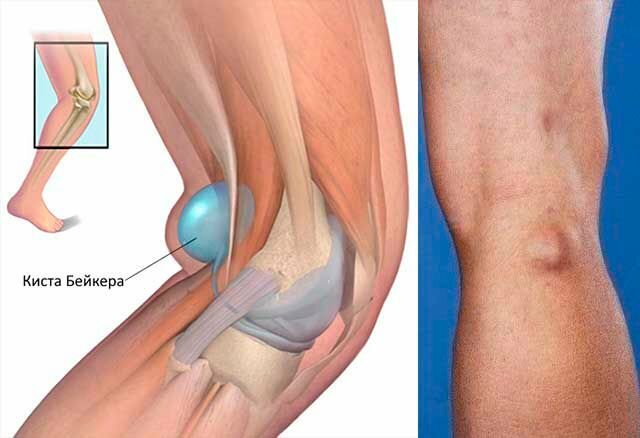

Заболевания и медицинские снимки: Жидкость в коленной чашечке